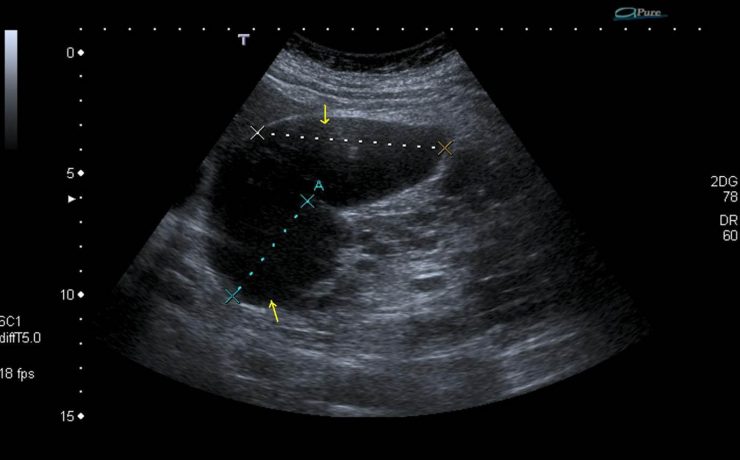

Escrito por Irene Arnanz González en 2014, hace la descripción de una paciente de 94 años quien ingresó a la consulta médica por prurito e ictericia con examen físico sospechoso por lo que se indicó ultrasonido de vías biliares con resultado de vesícula con pared gruesa de hasta 1cm de